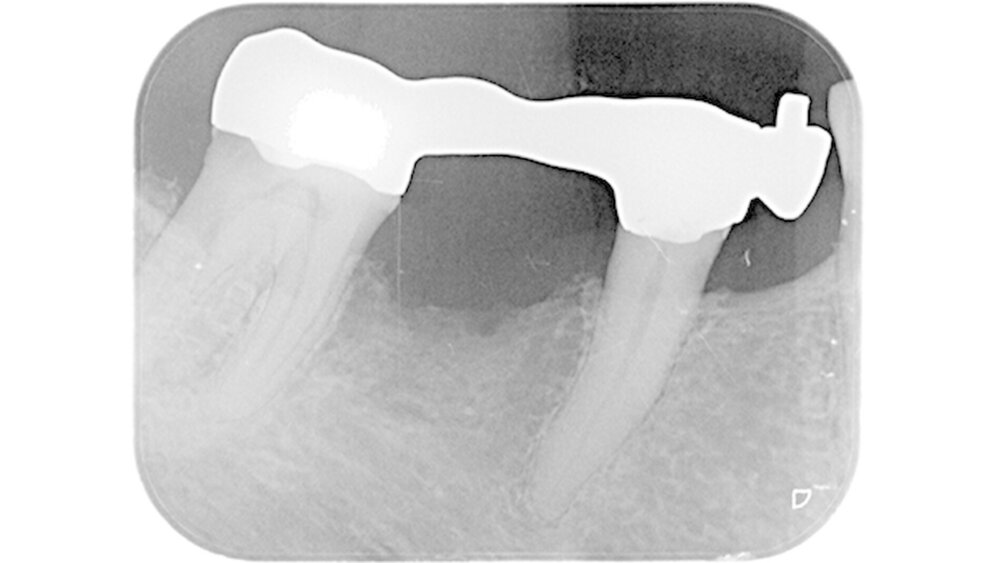

Kurioses: Die 50-jährige Brücke

Inzwischen sind die Studenten von einst - der angehende Zahnmediziner und der Pädagoge in spe - seit einigen Jahren im Ruhestand. Die Behandlung in der Klinik war der Beginn einer Freundschaft, die bis heute besteht. Die Brücke 47-45 mit Anhänger 44 wurde Mitte der 1960er als studentisches Erstlingswerk an der Universtätszahnklinik in Marburg eingegliedert - sie ist bis heute intakt, wie das Röntgenbild zeigt.